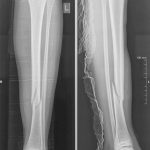

Այս ուսումնասիրությունը հիմնված է 21 հիվանդների (17 տղա, 4 աղջիկ) շարունակական խմբի բուժման արդյունքների վերլուծության վրա, որոնք ենթարկվել են տիտանե էլաստիկ մեխերով վիրահատության։ Հիվանդների տարիքը եղել է 4 տարեկանից մինչև 16 տարեկան։ 9 երեխայի մոտ կոտրվածքի պատճառ է հանդիսացել ձեռքի վրա անկումը, մնացածի մոտ կոտրվածքն առաջացել է վերջույթի ոլորման արդյունքում, վնասվածքի մեխանիզմը եղել է ուղիղ: 19 դեպքերում կոտրվածքները եղել են փակ, իսկ 2 դեպքում՝ բաց։ Ըստ վնասվածքի տեղայնացման՝ դրանք եղել են դիաֆիզար կոտրվածքներ (15 դեպք), պրոքսիմալ մետաֆիզի մակարդակի կոտրվածք (3 դեպք) և հեռավոր մետաֆիզի՝ (3 դեպք): Կոտրվածքային գծի բնույթի համաձայն՝ դիաֆիզային կոտրվածքներից հայտնաբերվել են 6 լայնակի, 4 թեք, 5 պտուտակաձև։ Մի տղայի մոտ (4 տարեկան), որի մոտ առկա էր սրունքի մ/3-ի բաց թեք կոտրվածք տեղաշարժով և մաշկի մինուս հյուսվածքներով, կատարվել է նաև վերքերի առաջնային վիրաբուժական մշակում և կարում՝ ռետինյա արտաթորիչներով։ Սակայն մի քանի շաբաթ անց սկսվել է մաշկի նեկրոզ։ Այդ իսկ կապակցությամբ կատարվել է երկրորդ վիրահատական միջամտությունը։ Կատարվել է մաշկի աուտոտրանսպլանտացիա։ Մաշկի կտորները վերցվել են առողջ ազդրի առաջային մակերեսից: (Նկ 1)

Երեխաները վիրահատված վերջույթը սկսել են օգտագործել առօրյա կյանքում (սնվել, հագնվել, հիգիենայի պարագաներ օգտագործել) օստեոսինթեզից 10-12 օր հետո։ Դպրոց հաճախելը վերսկսվել է հիվանդանոցից դուրս գրվելուց 7-10 օր հետո: Վիրահատված վերջույթի շարժման տիրույթի ամբողջական վերականգնում նկատվել է բոլոր երեխաների մոտ վիրահատական բուժումից 4-5 շաբաթ անց՝ անկախ կոտրվածքի բնույթից։ Սպորտին վերադարձը տեղի է ունեցել վիրահատությունից հետո 6 շաբաթից մինչև 3 ամիս ընկած ժամանակահատվածում՝ կախված սպորտի տեսակից և կոտրվածքի բնույթից։ Ինտրամեդուլյար մեխերի հեռացումը կատարվել է 15 դեպքերում օստեոսինթեզից 6 և ավելի ամիս անց, իսկ մնացած դեպքերում 12 ամիս անց։ Իմպլանտը հեռացվել է ընդհանուր անզգայացման տակ։ Իմպլանտի հեռացման ընթացքում կամ դրանից հետո բարդություններ չեն եղել: Բուժման ավարտից և իմպլանտների հեռացումից հետո հիվանդների արդյունքները գնահատելիս բոլոր դեպքերում գրանցվել է գերազանց արդյունք։ Հանդիպած բարդություններից եղել է 2 դեպք։ Մեկը՝ մաշկի նեկրոզ, որը պայմանավորված էր մեծ վերքի առկայությամբ կապված վնասվածքի բնույթից (ավտովրաերթ), և երկրորդը՝ ձողով մաշկի պերֆորացիա և թարախակալում։